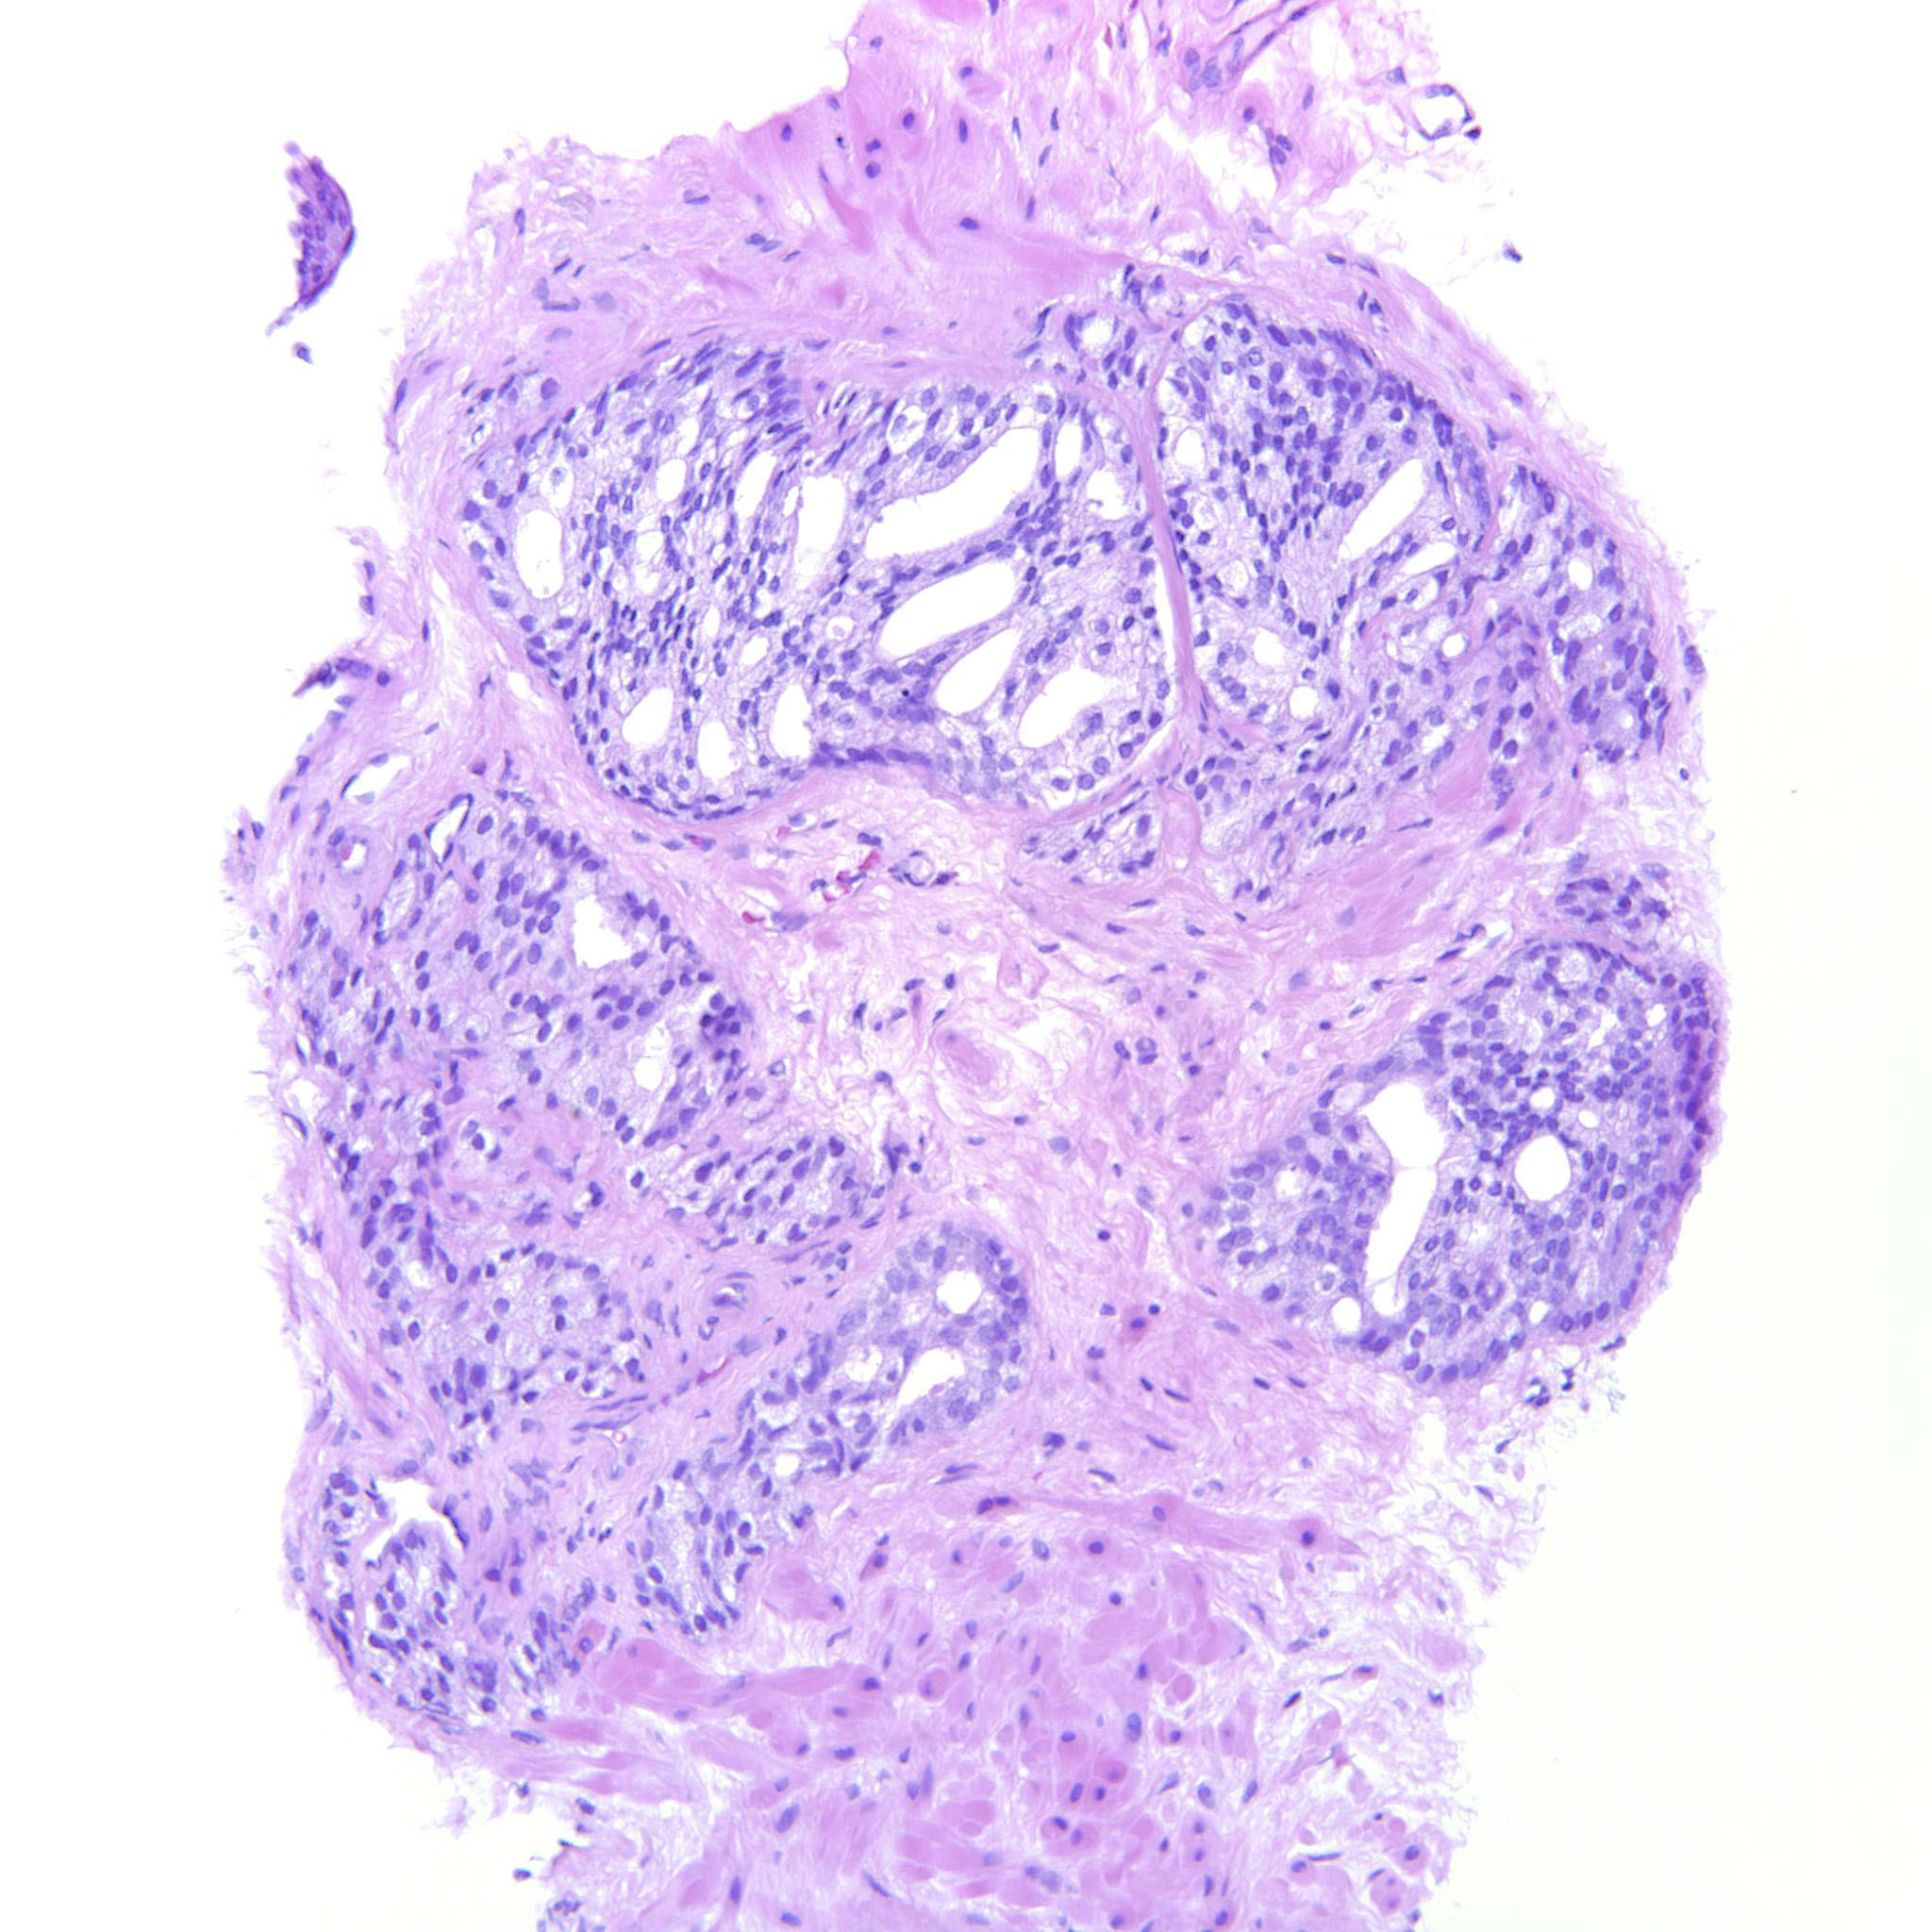

Prostate cancer grading

Case ID: 275